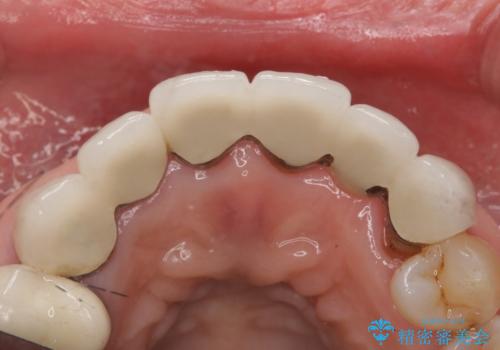

被せ物を除去したところ根管治療後の処置が不十分であったため、ファイバーコア(金属を用いない強くてしなやか材質の土台)を植立したのち、ジルコニアセラミッククラウンによる治療を行いました。

また、古い被せ物はブリッジではない右上321も連結されていましたが、1本1本の歯の動揺がなく連結する必要がないと判断し単冠による補綴を行いました。

被せ物の種類:ジルコニアセラミッククラウン スタンダード